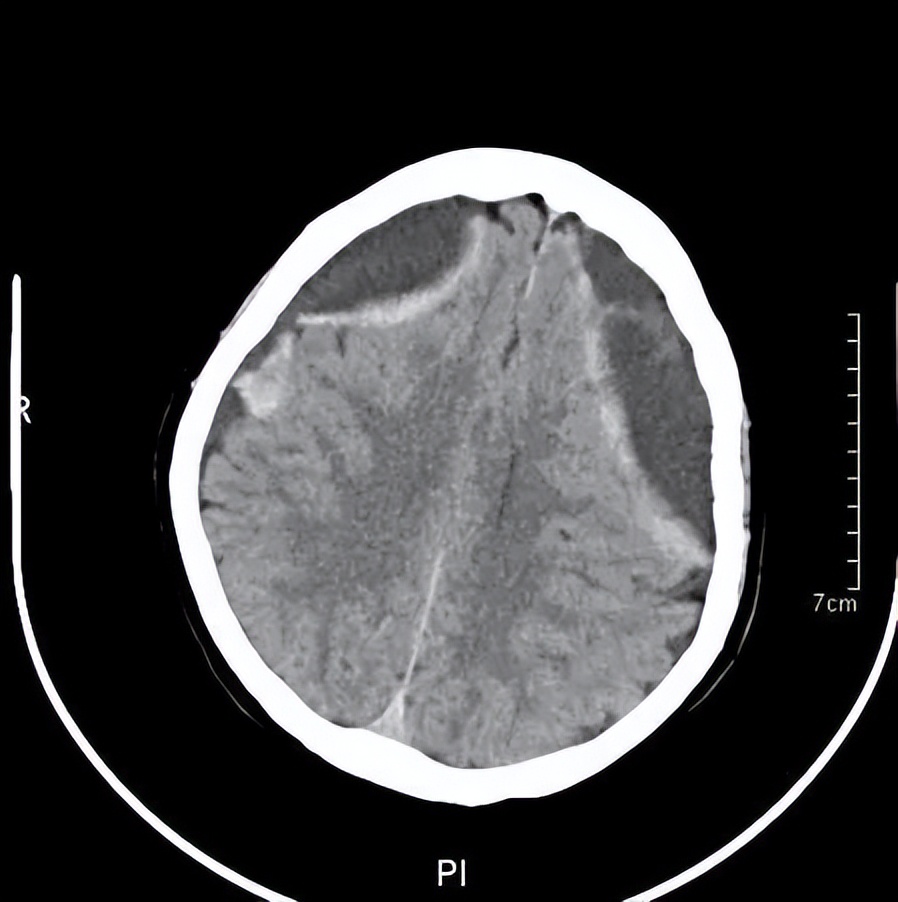

王阿婆门诊的头颅CT

黄主任询问了王阿婆的病史,给她做了简单的神经检查和认知测试,给王阿婆安排了急诊CT检查。结果显示,王阿婆的脑部有两处出血,报告为“双侧慢性硬膜下血肿”,需尽快神经外科住院治疗。神经外科建议王阿婆接受一个叫做“双侧钻孔引流”的手术。需在王阿婆的头部钻两个小孔,把血肿引流出来,手术并不复杂,但是需要专业的神经外科医生来执行。